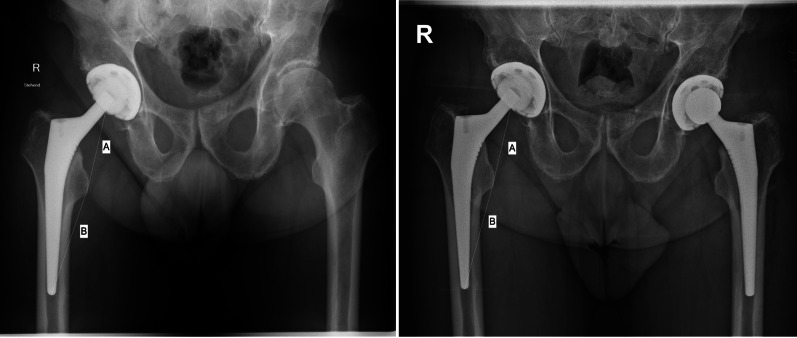

Methods: The present study was conducted following the STROBE guidelines. The records of patients who underwent THA between 2016 and 2023 were accessed. All patients who underwent two-staged bilateral THA were retrieved. The direct contact between the stem and the cortical bone was assessed at various points in the metaphysis and the distal portion of the stem (diaphysis) in both anteroposterior radiographs of the pelvis (medial and lateral bone contact) and a Lauenstein view of the hip (anterior and posterior bone contact). The following parameters were measured and compared to assess stem subsidence: distance from the proximal femur at the stem bone interface and the tip of the lesser trochanter (distance A); distance from the tip of the lesser trochanter and the tip of the femoral stem (distance B).

Results: In total, 250 patients were included, 45% (149 of 250 patients) were women and 61% (153 of 250 THAs) were implanted primarily on the right side. The mean age of patients at the time of the first THA was 64.3 ± 10.0 years and the mean body mass index (BMI) was 28.0 ± 4.9 kg/m2. The mean length of the follow-up was 14.1 ± 10.8 months. The overall stem subsidence following THA was 2.8 ± 0.7 mm (P < 0.006). A direct cortical bone-implant contact did not exert a statistically significant difference in subsidence of the THA stem at the metaphysis and diaphysis (P > 0.5). Stem subsidence following THA with a collarless cementless Corail stem was approximately 2.8 mm at 14 months.